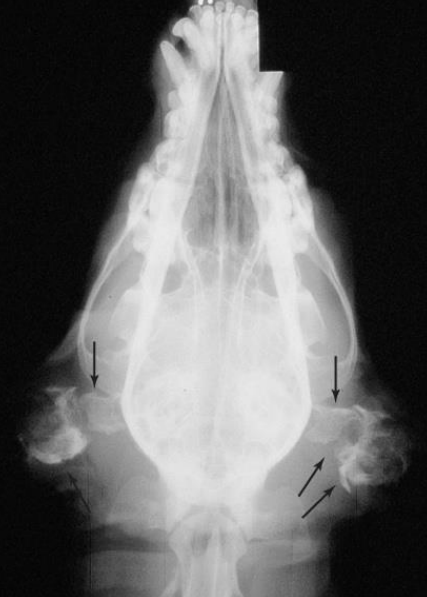

| Radiographs & CT | |

| - Open mouth view → 방사선 - 칼슘화 확인 | ==CT : tympanic cavity, 중이== 확인 - 정상일 때는 연골이 크게 변하지 않지만, 칼슘화되면 많이 변함. - 심각할 때 (많이 부어있고, 이도 막혀 있고, 냄새 나고 등) CT를 통해 중이를 확인해야 함. - vertical/horizontal ear canal의 mass 확인 등 | |

- 방사선, CT : concurrent otitis media, calcification, bone lysis (neoplasia)

이도가 뼈처럼 보임.